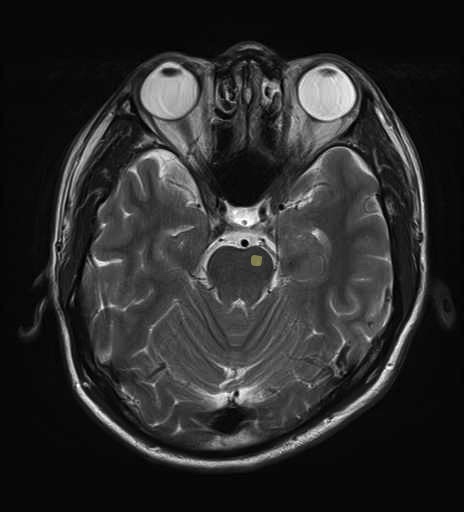

運動系 錐体路系に色を付けました。

■皮質脊髄路(いわゆる錐体路):一次運動野から脊髄遠隔の下位運動ニューロン細胞体まで

■皮質核路:一次運動野から橋及び脊髄神経核まで